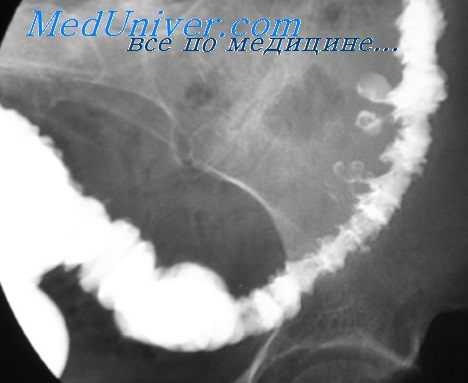

Процесс прохождения глотков бариевой взвеси (или специального бариевого препарата) регистрируют с помощью флюороскопии в реальном масштабе времени. Частое показание к рентгенологическому исследованию пищевода - диагностика желудочно-пищеводного рефлюкса. Он проявляется обратным забросом бариевой взвеси из желудка в пищевод при исследовании в горизонтальном положении или в положении Тренделенбурга. В случае обструкции пищевода инородным телом рентгенологическое исследование позволяет немедленно установить его уровень и выраженность. С помощью этого метода хорошо видны участки расширения и сужения пищевода при доброкачественных стриктурах (рубцовых, ахалазии). Для ахалазии характерно расширение проксимальной части пищевода и сужение его дистального отдела в форме «клюва». При опухолях пищевода (доброкачественных и злокачественных) виден дефект наполнения пищевода. Характерным признаком злокачественных образований (рака) является изъязвление слизистой и изменение ее рентгенологического рисунка, ригидность стенок пищевода, неровные контуры опухоли

Классическим показанием к рентгенологическому исследованию желудка является диагностика язв желудка и 12-перстной кишки. Язвы желудка чаще всего локализуются на малой кривизне, а 12-перстной кишки - в области ее луковицы. Однако возможна любая локализация язв. Наиболее надежными рентгенологическими симптомами язв являются симптомы «ниши» и «кратера», локальные изменения рисунка слизистой, отек и ригидность стенки в месте локализации язвы